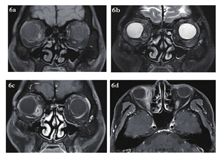

急诊入院者16例,6例患者行了MRI检查,主要为CT发现絮状密度影等感染征象、未发现异物影的,2例MRI发现异物影(图4a~d)。早期入院者7例,5例行了MRI检查(包括3例CT未发现异物的患者),其中3例发现异物影。其主要表现为:T1WI呈等信号或低信号,T2WI呈等信号,增强时中央无强化影,周边强化(图5a~d);中晚期入院者19例,16例行了眼眶MRI检查(未行MRI检查的为CT明确发现异物的)。其中15例患者发现异物影(93.8%),主要表现为:T1WI呈低信号,T2WI呈等信号或混杂高信号表现,增强时多表现为病灶中央无强化影(异物,不强化),周边明显强化(冠状位的典型表现为环状增强)(图6a~d)。